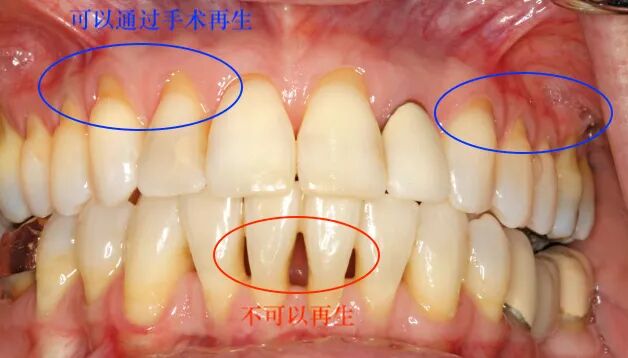

6. 牙周病如何治疗?